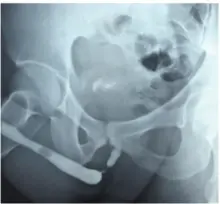

Απεικόνιση 2     Μπαλόνι διαστολής Optilume. Η ιδιαιτερότητα του μπαλονιού  αυτού έγκειται στο κυτταροστατικό φάρμακο πακλιταξέλη, το οποίο επαλείφει τα εξωτερικά τοιχώματα του μπαλονιού και εμφυτεύεται κατά τη διαστολή του μπαλονιού κυκλικά σε όλη την επιφάνεια της ουλής.